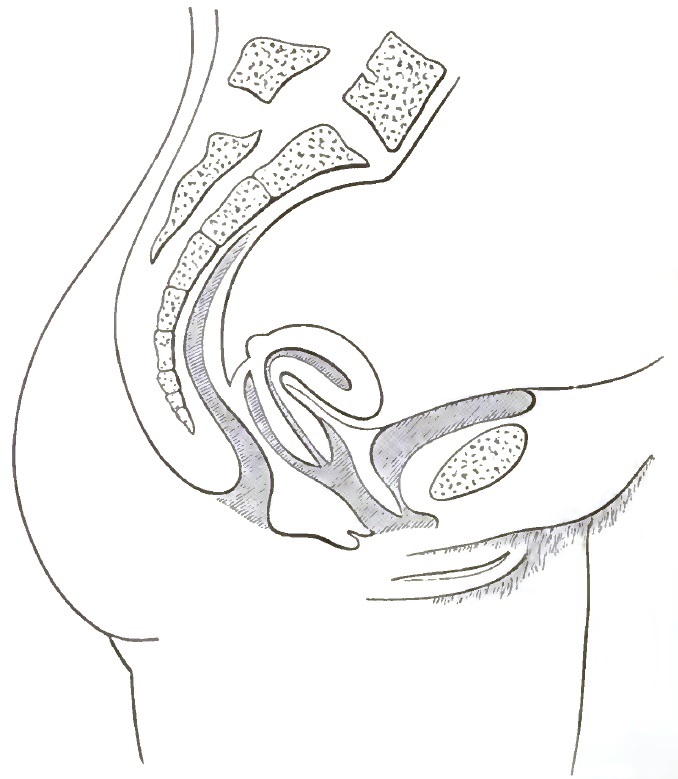

| 3. | FIRST DEGREE OF PROLAPSE OF THE POST-PARTUM UTERUS |